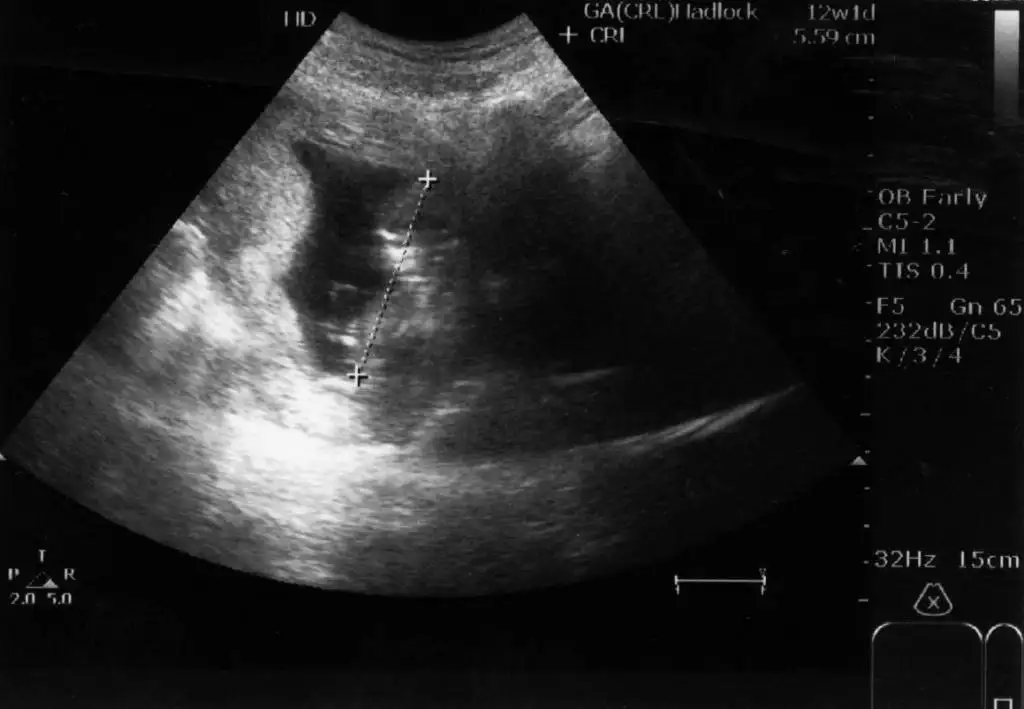

ORKDM yazdıklarınızı okuyunca ben de bebeğimin geçen hafta çekilen ultrason görüntüsüne baktım.

Doktor ''henüz kesin değil ama kıza benziyor'' demişti.Şimdi bakınca gördüm ki;paralel duruyor.

Bu durumda kız olcak gibi görünüyor.

Kesinleşince yazarım.